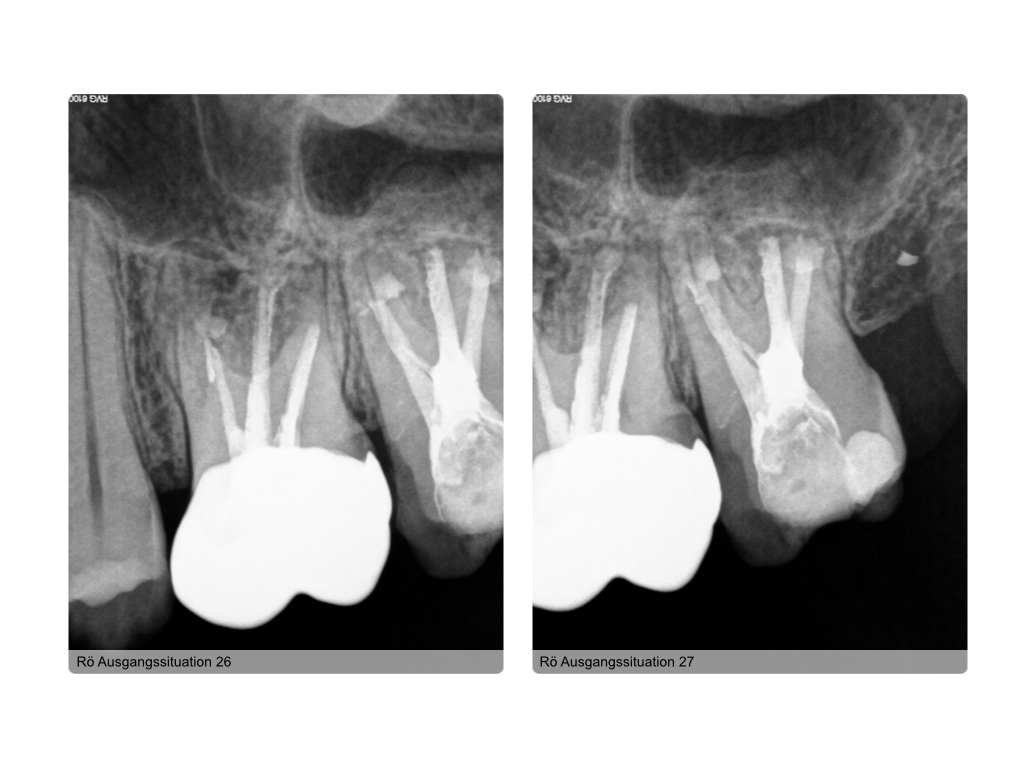

Zustand nach WSR